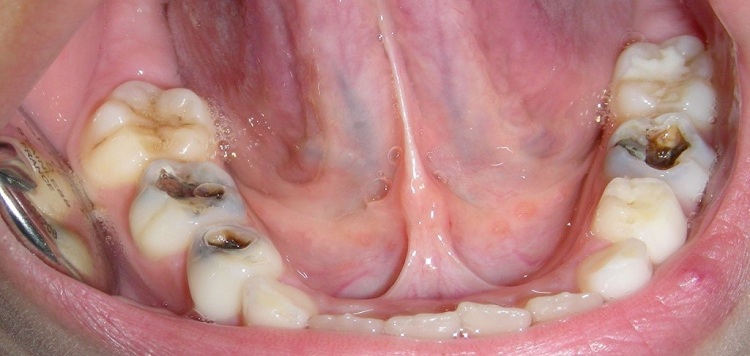

Prevention of dental caries